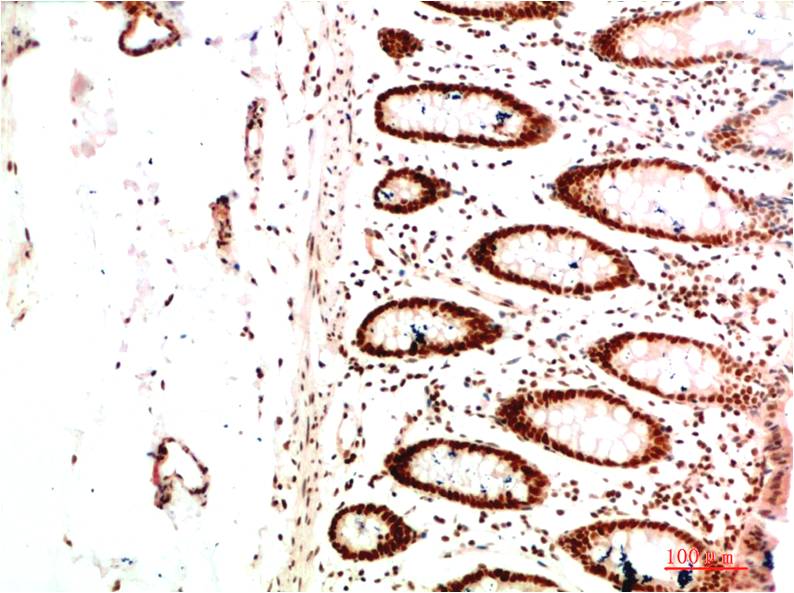

HP-1α Mouse Monoclonal Antibody(5E3)

Catalog NO.:BE3698

Applications :WB, IHC

Reactivity :H,R,M

Heterochromatin protein 1 (HP1) is a family of heterochromatic adaptor molecules involved in both gene silencing and higher order chromatin structure. All three HP1 family members (α, β, and γ) are primarily associated with centromeric heterochromatin.

Recommended dilutions: WB 1:500-1,000 IHC 1:200-500